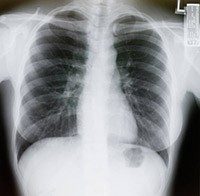

What to expect during a CT scan

CT scans or CAT scans are a crucial part of the cancer diagnosis and cancer treatment process. A CT scan takes X-ray images from multiple...